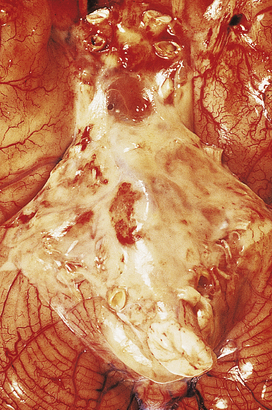

Examination of the CSF by lumbar puncture is essential in each case; the main CSF changes in the CNS infections are listed in Table 26.6. The CSF in bacterial meningitis usually contains many organisms, although these are sometimes detected only on culture. In fatal cases, pus is present in the cerebral sulci and around the base of the brain, extending down around the spinal cord (Fig. 26.13).

image

Fig. 26.13 Bacterial meningitis: basal exudate. In this example of pyogenic meningitis due to Escherichia coli, a dense acute inflammatory exudate is present around the brainstem, cerebellum and adjacent structures at the base of the brain. Obstruction of the fourth ventricle exit foramina resulted in acute hydrocephalus in this case.

The meningeal and superficial cortical blood vessels are congested, often with small foci of perivascular haemorrhage. The CSF is usually turbid, even in the ventricles, which often show signs of acute inflammation with fibrin deposition. Common complications of bacterial meningitis are: